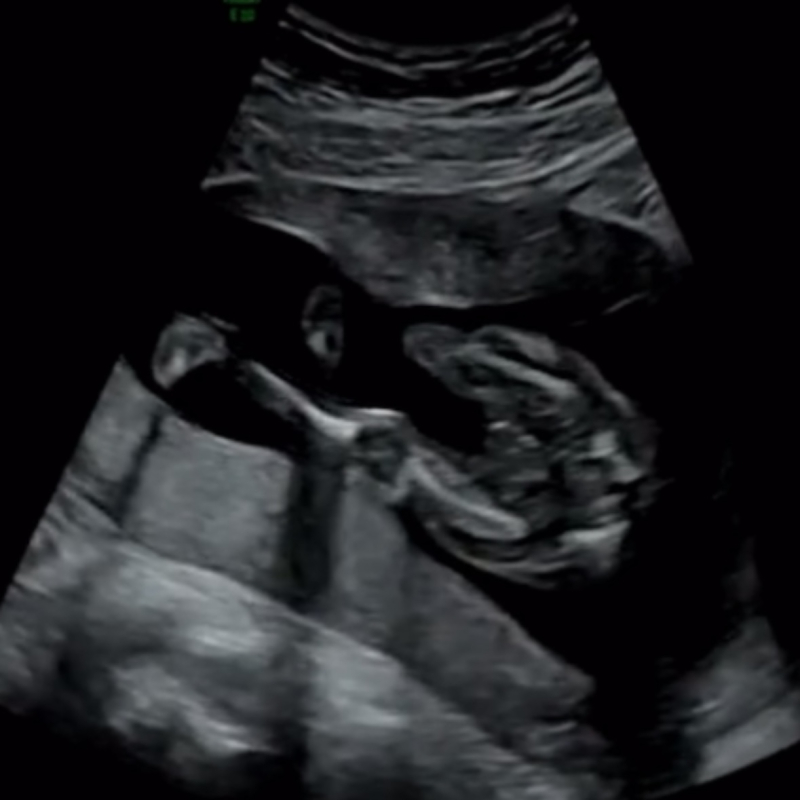

エコーの写真だけで、性別をお答えするのは、間違いがあってもよくないので、控えさせていただいております🙇